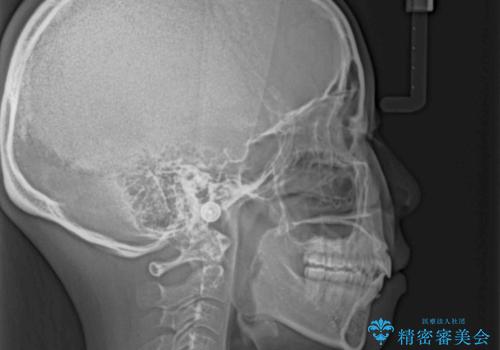

上下前歯が著しく前突している状態であったので、上下左右の第1小臼歯4本を抜歯し、ワイヤー装置にて矯正治療を行うこととしました。

舌の突出癖により、前突になったと考えられたため、舌のトレーニングをしっかりと行うよう指導しました。

4本の歯を抜歯したことで、飛び出していた口元が引っ込み、横顔が大きく改善されました。